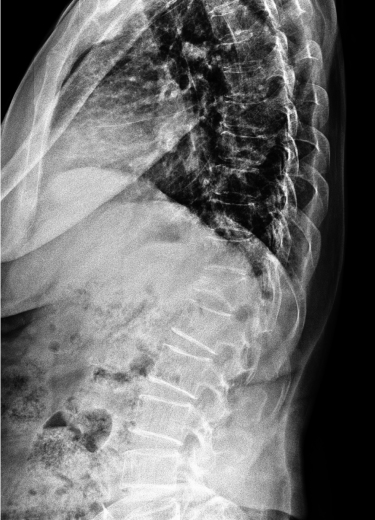

척추 골절

교통사고나 낙상 등에 의한 충격에 척추 골절이 발생하기도 하며, 대부분 고연령층에서 골다공증성 골절로 발생하는 경우가 많습니다.

척추압박골절은 골절 유합은 물론 장기적인 합병증이 발생하지 않도록 주의해야 합니다.

또, 대부분 고령 환자이거나 내과적 기저질환을 앓고 있는 환자로 심각함 골다공증 상태에서 척추 손상이 재발하면 추가적인 골절 위험성이 매우 크므로 골절 치료뿐 아니라 주기적인 골다공증 검사 및 예방으로 환자의 전신상태를 관리해 주는 게 중요합니다.

척추 골절에서 발생하는 문제점

□ 2차적인 변형을 초래할 수 있어 이로 인해 신경압박이나 만성 신경병증 후유증이 남을 수 있음

2021.12.21

2021.12.27